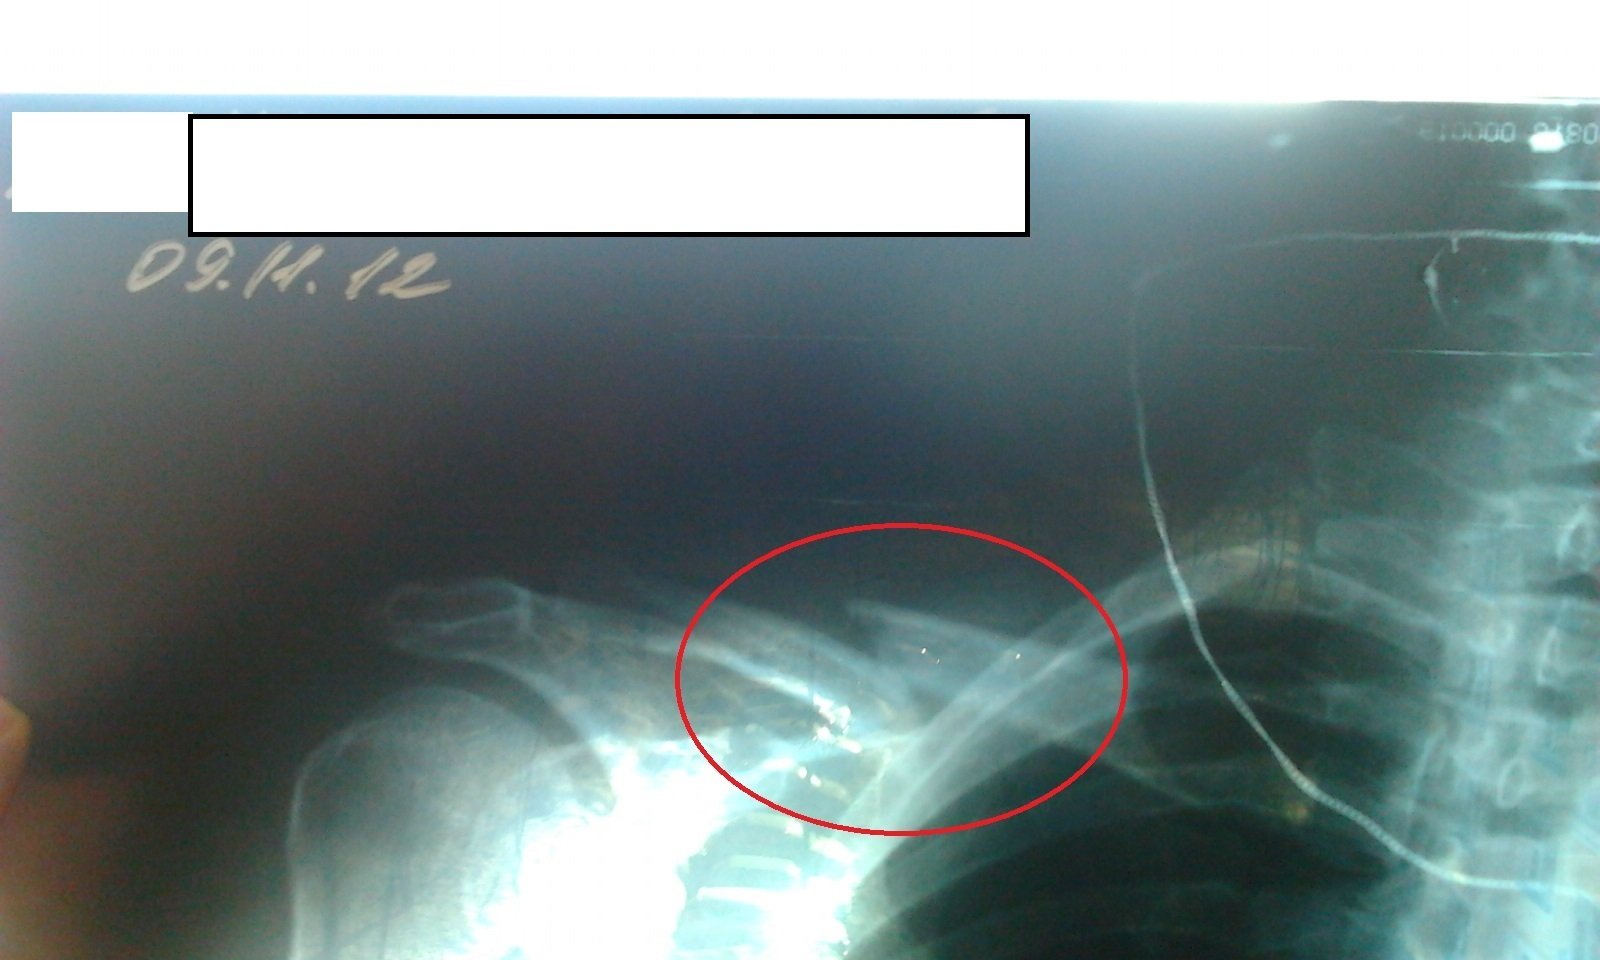

ЭТОТ СНИМОК Я РАЗМЕСТИЛА, В ОТВЕТ НА ОБВИНЕНИЯ В ТРОЛЛИНГЕ НЕКОЕГО ВИКТОРА! Исключительно, для того, чтобы подтвердить, что я знаю, о чем говорю, оставляя свой первый комментарий в этом отзыве (а не просто чешу языком про перфорацию легкого), так как сама недавно общалась с врачами по такой же травме!

Перелом ключицы со смещением на горнолыжном курорте. Страховка спортивная, покрытие 30000 евро, без франшизы. Факты:14-10 страховой случай, 14-30 зарегестрировались, за это время приехала скорая и отвезла нас в ближайшую клинику, 15 минут, до 14-45 мы висели на телефоне — никто, ничего не знал. В клинике сделали обезболивающий укол, рентген, наложили повязку. Сказали, что нужна хирургическая операция. Позвонили еще раз в РОСГОССТРАХ. Они сказали ждите. Мы ждали до 18-40. За это время проходили люди, белые люди, немцы, англичане, итальянцы, которые имели страховки нормальных компаний. амы сидели и ждали. Нам никто не звонил и вот 18-40. Звонит некто и представляется Михаилом и говорит, наш врач сказал, что Вам операция не нужна. Вы можете потерпеть до Москвы. А там идите в свою клинику и делайте ее но уже не за наш счет и тд. и тп. Слова не давал вставить. Еще разговор на 40 минут. После чего он согласился найти не дорогую клинику в окрестностях за 20 минут. Естественно не перезвонил. Мы нашли общественную клинику в 45 километрах и позвонили ему. На вопрос почему вы не перезвонили последовал резанный ответ — вы же у меня не одни. На что мы естественно согласились. Наконец, минут через 20 разговоров он подтвердил осмотр в той клинике. Мы вызвали очередную скорую, оплатили пребывание в предыдущей клинике и проследовали во вторую. Там снова ренген, переговоры, отсутствие мест для госпитализации и обещание утром перезвонить и решить наш вопрос. Я думаю вы уже догадались, что звонок Михаила Юрьевича Радченко мы до сих пор ждем.

«Классный» врач! По телефону видит нужна операция или нет. На всякий случай… при сложных переломах ключицы со смещением бывает угроза перфорации легкого. Без срочной операции возможен летальный исход((

В этом случае может быть не только перфорация легкого, но и более грозное осложнение — повреждение подключичной вены или, что более опасно, Артерии. Поэтому операция необходима по жизненным показаниям!